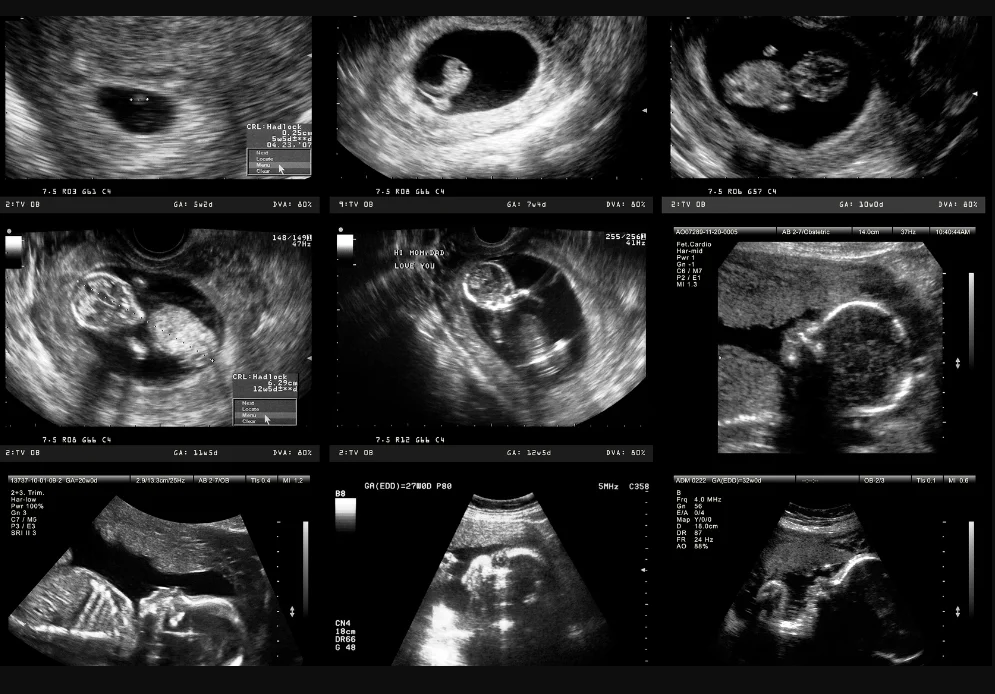

บันทึก Ultrasound

เก็บภาพและวิดีออัลตราซาวด์ในระบบได้ เพื่อดูย้อนหลังและวิเคราะห์การตั้งครรภ์อย่างมีประสิทธิภาพ